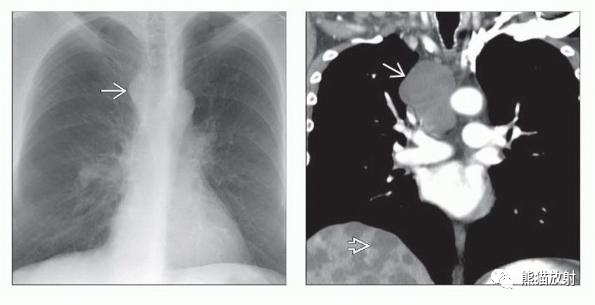

(左) 支气管型囊肿患者的PA胸片显示纵隔右上缘气管旁线异常增厚、凸起。

(右) 同一患者的冠状位CECT显示一个大的气管右旁支气管源性囊肿,均匀液性密度,另见多发无关的肝囊肿。

支气管性囊肿常表现为液体密度,可有难以察觉的囊壁(如本例),常邻近气管或隆突。